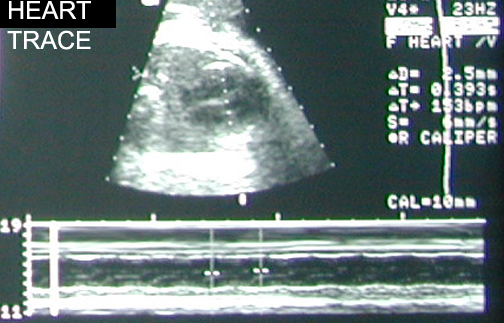

Doppler Fetal heart. Identify heart, descending aorta, carotid artery. Answer

Fetal heart

Heart trace